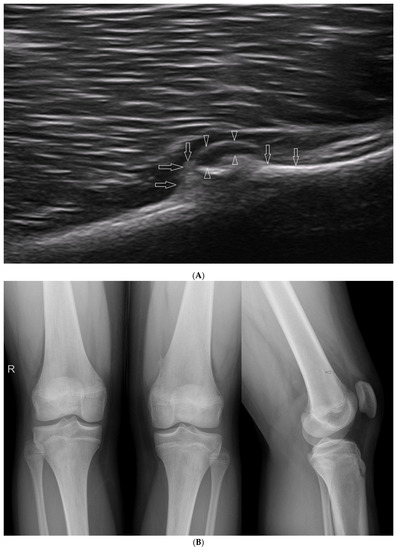

We present basic differences in the musculoskeletal ultrasound examinations between adults and children. Examiners who deal with adults on a daily basis have shared concerns about examining children. Such concerns may arise from the different approach to child ultrasounds, but they also come [...] Read more.

We present basic differences in the musculoskeletal ultrasound examinations between adults and children. Examiners who deal with adults on a daily basis have shared concerns about examining children. Such concerns may arise from the different approach to child ultrasounds, but they also come from differences in anatomical characteristics according to developmental age. We discuss the presence of growth plates, as well as non-mineralized parts of the bones. We also refer to the pathologies most often found in ultrasounds in early developmental stages. In the PubMed database, the set of keywords: “msk ultrasound in children”, “pediatric msk sonoanatomy”, “coxitis fugax”, “pediatric Baker’s cyst”, “Baker’s cyst ultrasonography”, “bone septic necrosis in ultrasonography”, “ultrasonography in juvenile idiopathic arthritis”, and “ultrasonography in juvenile spondyloarthropathies”, was used to identify a total of 1657 results, from which 54 was selected to be included in the article. We discuss the problem of osteochondritis dissecans, Osgood-Schlatter disease, examples of ligament injuries (especially in relation to the knee and ankle joints), exfoliation of growth cartilages, osteochondroma, exudates and inflammations affecting joints, and Baker’s cysts. In this way, we have collected useful information about the most common diseases of the musculoskeletal system in children. Full article